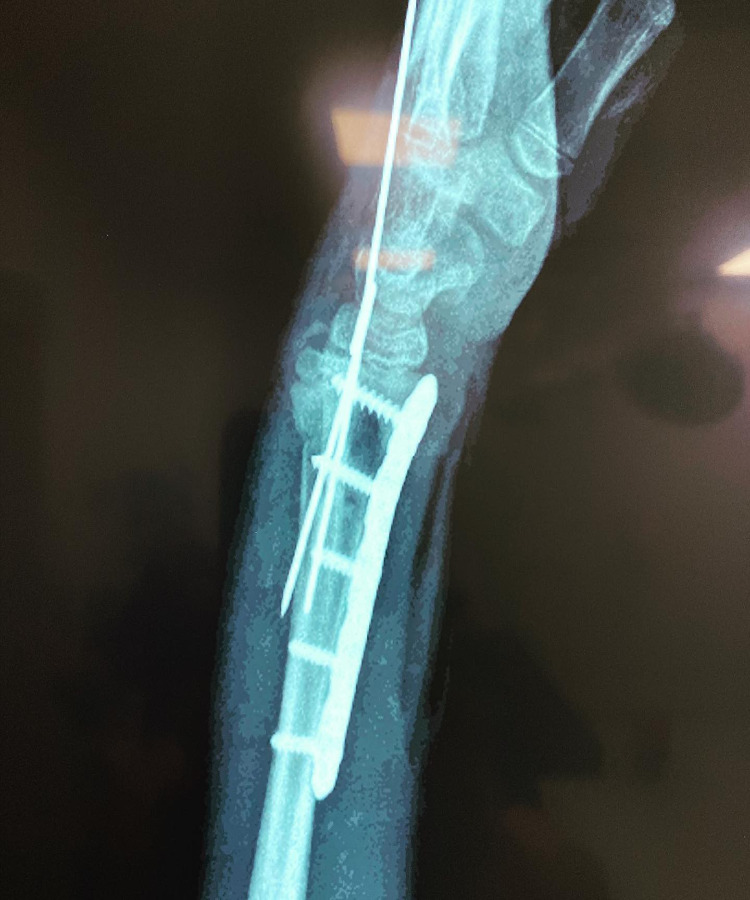

Técnicas quirúrgicas pediátricas restauran función y apariencia de extremidades con lesiones graves o deformidades congénitas, buscando mejorar funcionalidad y estética.

Las fracturas en niños son comunes y pueden afectar su crecimiento si no se tratan debido a las características únicas de sus huesos en desarrollo.